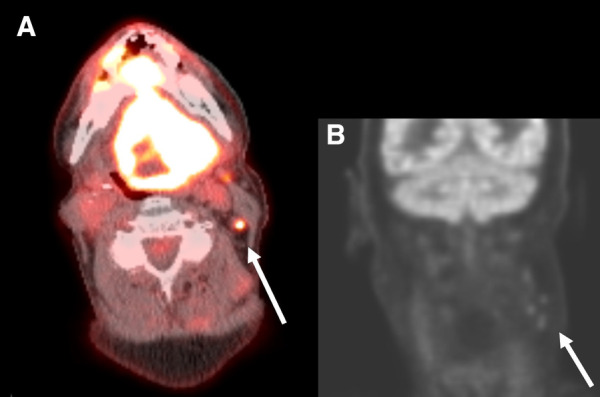

Abstract Image